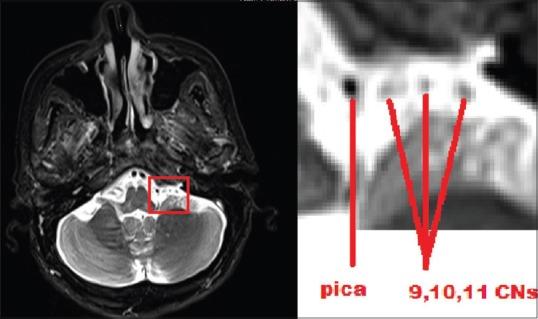

Vascular compression has been reported to be the most common reason for vago-glossopharyngeal neuralgia (VGN). The treatment may include medications, ganglion blockade with a radiofrequency ablation, and microvascular decompression (MVD). A review of the literature reveals that VGN may develop due to choroid plexus compression, and the number of reported cases is very limited. The current case is the fifth in the relevant literature. In this paper, choroid plexus compression has been shown intraoperatively during the treatment of rare idiopathic VGN using MVD. Complaints of the patient have been resolved following the choroid plexus excision.

据报道,血管压迫是迷走神经 - 舌咽神经痛(VGN)最常见的原因。治疗方法可能包括药物治疗、射频消融神经节阻滞和微血管减压术(MVD)。文献综述显示,VGN可能由于脉络丛受压而发生,且报道的病例数量非常有限。本病例是相关文献中的第五例。本文展示了在使用MVD治疗罕见的特发性VGN过程中,术中发现脉络丛受压。切除脉络丛后患者的症状得到缓解。